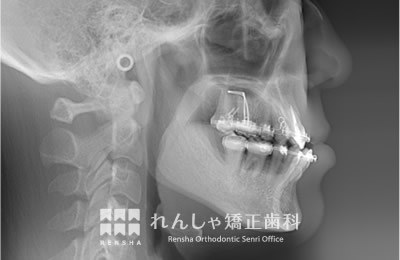

大人

軽度の上顎前突であれば、上奥歯の後方移動で前歯の前突を改善することもありますが、上顎前突は叢生の問題も絡んでいることがほとんどで、永久歯の抜歯が必要になることがあります。また上奥歯の後方移動には矯正矯正用アンカースクリューの併用が効果的です。

治療前

| 主訴 | 出っ歯と前歯のがたつき |

|---|---|

| 診断名 | Angle Class II 上顎前突 |

| 初診時年齢 | 20歳7か月 |

| 装置名 | マルチブラケット装置 矯正用アンカースクリュー |

| 抜歯非抜歯 | 上下顎左右第二小臼歯の抜歯(合計4本) |

| 治療期間 | 3年2か月 |

| 費用の目安 | 約75万円+消費税(検査料金、都度の処置費用等も合わせた総額) |

| リスク副作用 | 歯の移動に伴う軽微な歯根吸収、歯槽骨吸収、歯肉退縮(本症例では軽度の歯肉退縮と歯根吸収を認めた)、矯正器具装着中のカリエスリスク増大(本症例では大臼歯にカリエスが発生し、その後う蝕処置)、上顎左側犬歯の失活 |